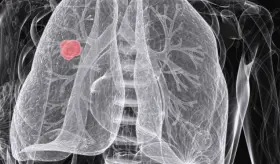

El análisis de 871 tumores pulmonares en no fumadores reveló que vivir en zonas contaminadas se asocia a mutaciones relacionadas con el envejecimiento y el tabaquismo, así como a telómeros más cortos, un signo de envejecimiento celular acelerado.

Aunque las tasas de tabaquismo han disminuido significativamente en las últimas décadas, el cáncer de pulmón vuelve a posicionarse como una de las principales causas de muerte por cáncer en el mundo.

Cirujanos torácicos han pedido implantar el cribado de cáncer de pulmón de forma "pública y universal", lo que permitiría detectar nódulos de este tumor en estadios tempranos.